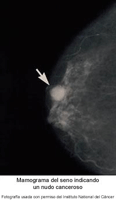

Mamografías y salud mamaria

La mamografía es una imagen radiográfica de las mamas. Se usa para detectar y diagnosticar las enfermedades mamarias. Pueden hacerle una mamografía si tiene problemas en las mamas, como un bulto, dolor o secreción del pezón. También puede hacerse como una prueba de detección si no tiene problemas en las mamas. Esta prueba puede detectar el cáncer de mama, tumores no cancerosos (o benignos) y quistes antes de que estos puedan palparse.

Una mamografía no puede probar que una zona anormal sea cáncer. Si, en una mamografía, puede verse una zona de la mama que sea anormal o que tal vez sea cancerosa, pueden hacerse pruebas de seguimiento, como una ecografía mamaria o una resonancia magnética. Para tener un diagnóstico concluyente, el proveedor de atención médica toma una muestra de tejido mamario (biopsia) con una aguja o durante una cirugía. El tejido se examinará en el laboratorio con un microscopio para ver si hay células cancerosas.

¿Qué afecciones se muestran en una mamografía?

Una mamografía puede mostrar las siguientes afecciones:

Puede haber masas con o sin calcificaciones. Las causas de las masas pueden ser las siguientes:

Cáncer de mama